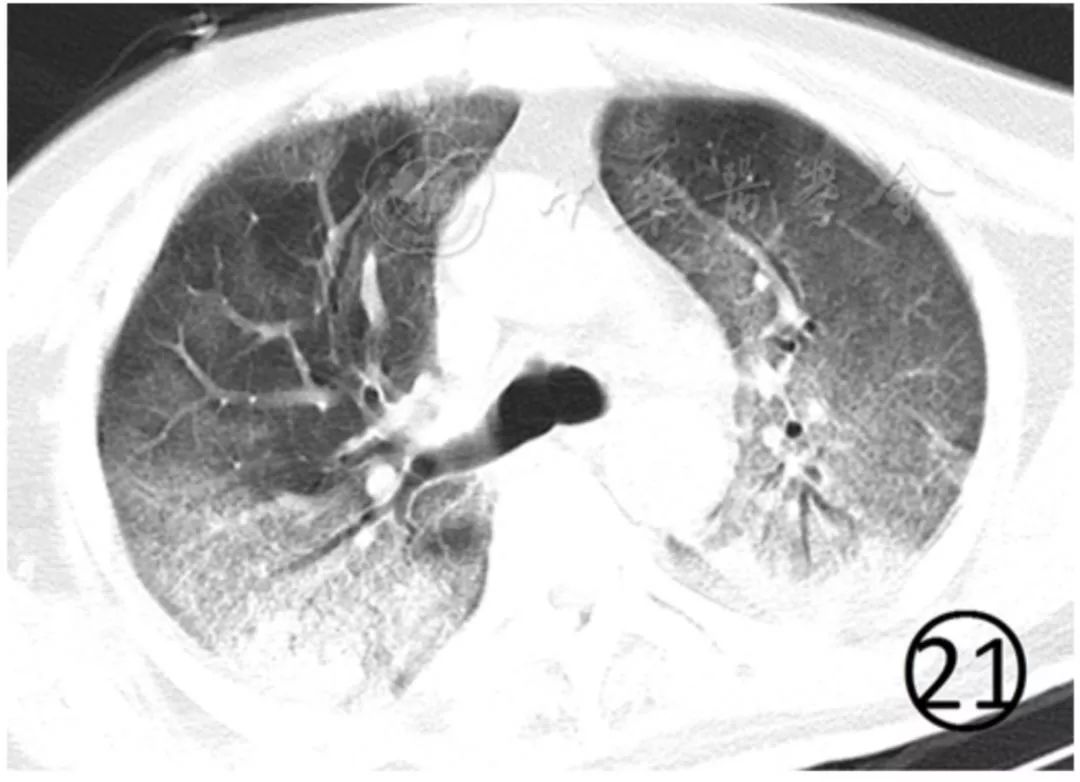

病变进一步进展,双肺弥漫性实变,密度不均,其内空气支气管征与支气管扩张,非实变区可呈斑片状磨玻璃阴影表现,双肺大部分受累时呈"白肺"表现(图21),叶间胸膜和双侧胸膜常见增厚,并少量胸腔积液,呈游离积液或局部包裹表现。

图21 男,60岁。CT平扫肺窗显示双肺大部分呈网格状磨玻璃影,背侧明显且部分密实,类"白肺"表现,可见空气支气管征